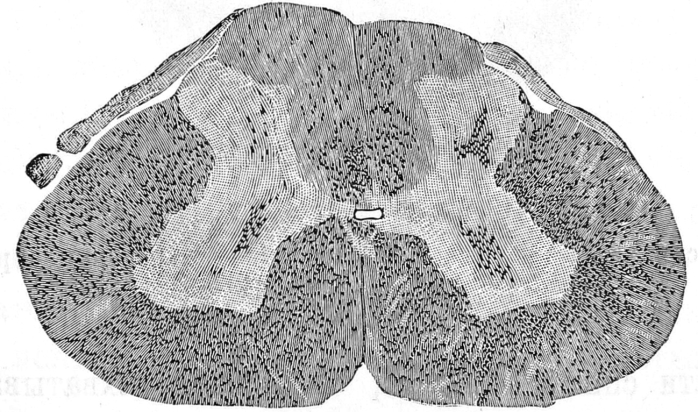

Въ самомъ дѣлѣ, спустя 6—8 дней послѣ перевязки брюшной аорты способъ Marchi указываетъ на диффузную тонко разсѣянную дегенерацію, которая не подходитъ подъ извѣстныя системы. Дегенерація главнымъ образомъ охватываетъ боковые пучки, гдѣ перерождена масса отдѣльныхъ волоконъ, узкую полоску на наружномъ краѣ переднихъ пучковъ, задніе пучки, гдѣ перерожденіе также тонко разсѣянное, далѣе дегенерація распространяется на медіальную часть Годлевскихъ пучковъ.